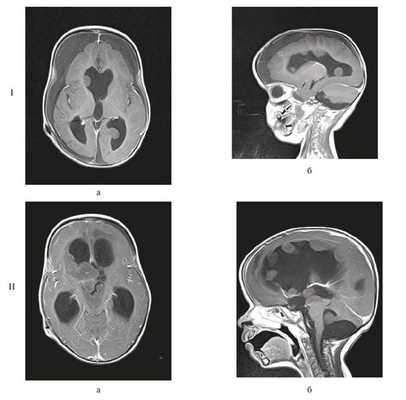

Через 3 нед была проведена полихимиотерапия (ПХТ) по Протоколу Baby-POG, всего проведено 3 цикла. При контрольной МРТ головного мозга выявлено множество узлов опухоли, распространяющихся по желудочковой системе в зоне операции (рис. 7).

![]()

Рисунок 7. МРТ головного мозга. I — после 1-го курса ПХТ (через 2 мес после радикального удаления опухоли); множество опухолевых узлов, распространяющихся по желудочковой системе; II — после 2-го курса ПХТ (через 9 мес после радикального удаления опухоли); метастазирование процесса (в виде многочисленных опухолевых узлов, распространяющихся по всей желудочковой системе). Режим Т1 с контрастным усилением: а— аксиальный срез; б — сагиттальный срез.

Протокол лечения был изменен на индивидуальную схему лечения таргетным препаратом Avastin в сочетании с химиопрепаратом Иринотекан (CAMPTO). Несмотря на проводимую ПХТ, при контрольной МРТ головного мозга выявлено метастазирование процесса в виде многочисленных опухолевых узлов, распространяющихся по всей желудочковой системе. Клинические и МРТ-признаки дисфункции шунта явились показаниями к ревизии и переустановке шунтирующей системы. Состояние ребенка несколько стабилизировалось, после чего был продолжен курс ПХТ. Несмотря на проводимое лечение, состояние ребенка прогрессивно ухудшалось, и девочка умерла спустя 9 мес после радикального удаления.